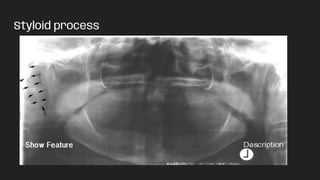

Styloid process

● Styloid process